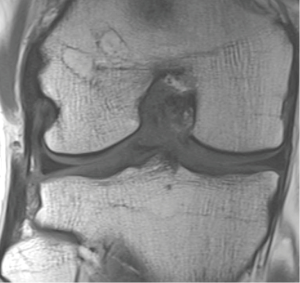

At the 2-year follow-up, the rotational stability was still the best among the patients with double-bundle ACL reconstruction. Also, the patients with the double-bundle ACL reconstruction had significantly fewer graft failures leading to revision ACL surgery than the patients with the single-bundle procedure (18). MRI evaluation at 2 years showed that there was less tunnel enlargement in each tunnel the tibial side in the patients with the double-bundle ACL reconstruction than in the patients with the single-bundle technique (17). In this study, bone tunnel enlargement was assessed digitally by measuring the widths of the bone tunnels perpendicular to the long axis of the tunnels on an oblique coronal and sagittal plane. The MRI were interpreted by consensus by two musculoskeletal radiologists who were unaware of the patients’ clinical data. The anteroposterior and mediolateral diameters of the femoral and tibial tunnels were measured 2 cm from the articular surface of the knee joint, and a mean of these two measurements was recorded. The measurements were repeated in 20 randomly chosen patients after 2 months, and the intraobserver differences were evaluated. The MRI data at follow-up were compared with the intraoperatively documented drill diameters. Changes in tunnel size were calculated in millimeters and as a percentage of the diameter of the drill size used at surgery. In another MRI study, tunnel communication was seen in the femur in 10% of patients and in the tibia in 27% of the patients, although no statistically significant association between the MRI findings of tunnel communication and knee laxity was found (35). In addition, MRI evaluation at 2 years showed that the patients with the single-bundle procedure had significantly more invisible grafts than the patients with the double-bundle procedure, although no revision ACL surgery was performed for them so far (26). Further analysis of the patients with the double-bundle ACL reconstruction showed that the graft disruption was seen only in 3% of AM grafts and 6% of PL grafts at 2 years. Both grafts were disrupted only in 3% of the patients (36). The locations of the grafts were determined with MRI at the 2-year follow-up by a musculoskeletal radiologist both in patients with the double-bundle ACL reconstruction and in patients with the single-bundle ACL reconstruction, and they were all at the anatomic zone of insertion sites of the ACL (37,38).

At the 5-year follow-up, there was no significant difference in the rotational stability of the knee anymore. However, the patients with the single-bundle ACL reconstruction had significantly more graft failures leading to the revision ACL surgery than the patients with the double-bundle technique. At 5 years, the x-rays showed no significant differences at osteoarthritic rates between the patients with the single-bundle and the double-bundle procedures (25). The MRI evaluation in the patients with the double-bundle ACL reconstruction showed that the tunnel enlargement seen at 2 years was followed by tunnel narrowing at 5-year follow-up. Tunnel ossification resulted in evenly narrowed tunnels in 44%, in conical tunnels in 48%, and fully ossified in 8%. At 5 years, none of the bioabsorbable screws was anymore completely visible, and 19% of them were already fully ossified (Figure 3) (39).